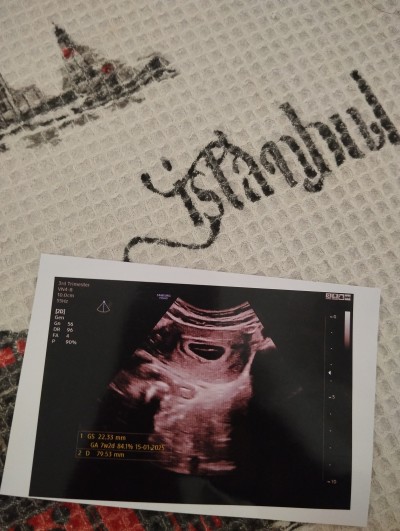

Kese 22mm ama bebek yok dedi daha doktor yolk saç var Mı sizce

Gebelik haftası 6+2

7-8 haftadan daha net görürsün ve kalp atışını da duyarsın. Şuan yok gibi görünüyor geç döllenme de olabilir kötü düşünme daha çok yeni